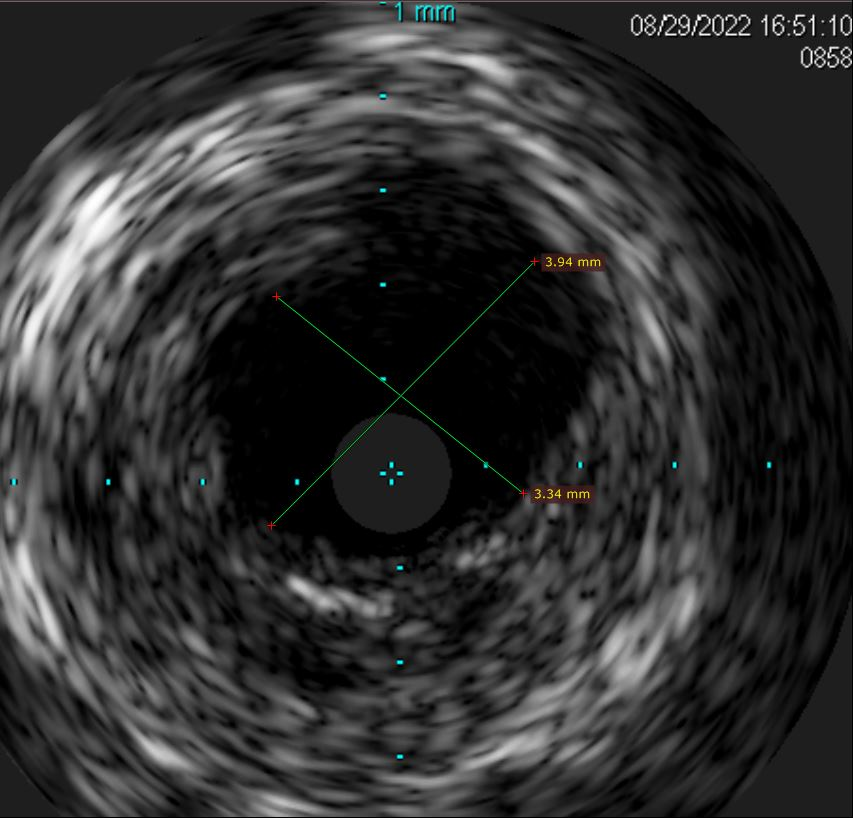

针对右上肺动脉狭窄病变采用小球囊逐级扩张,后用相应直径的割球囊再次扩张,达到预期后,再用药物球囊贴壁扩张,释放抗炎,防增生药物,以巩固治疗效果。全程应用肺动脉相控阵血管内超声(IVUS)显示右上肺动脉狭窄病变,同时准确测量需要球囊扩张的靶病变长度,避免血管损害,保证安全性。

经治疗后右上肺近端狭窄病变血管经相控阵血管内超声(IVUS)测量明显扩大,血流恢复到正常水平。